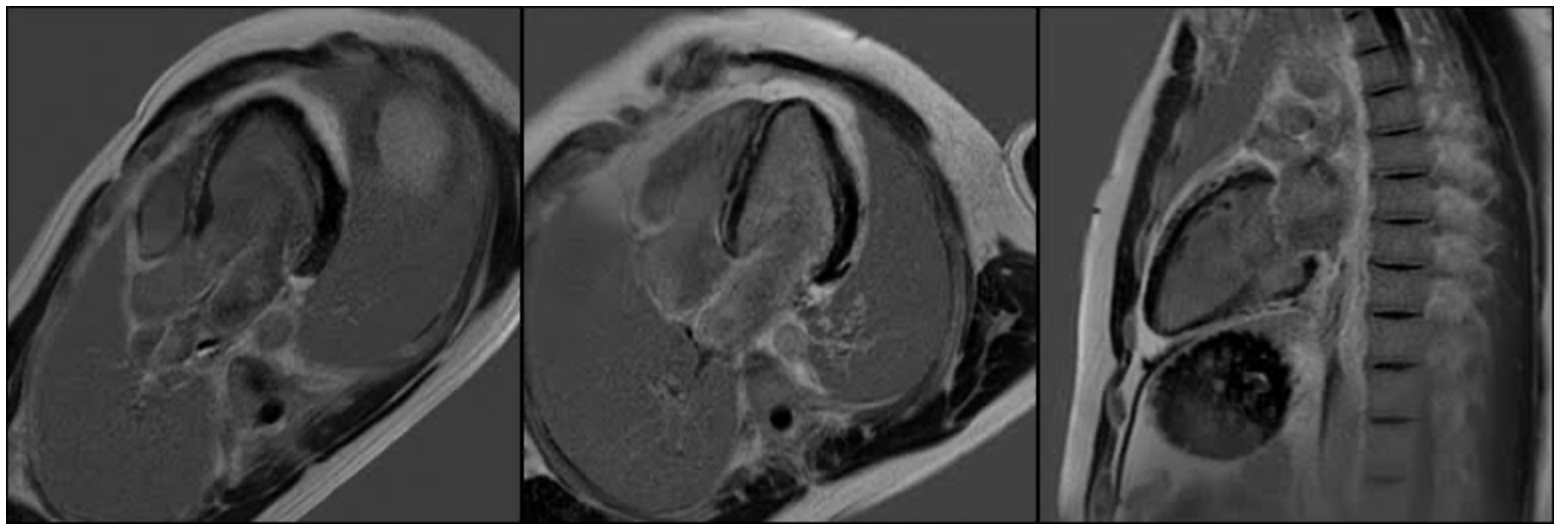

Figure 2. LGE sequences in standard 3-, 4-, and 2-chamber views, highlighting the extent, pattern, and regional distribution of enhancement in the left ventricular myocardium.